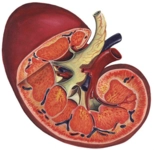

Böbrek Yetmezliği Raporuna Göre Engel Oranı Nedir 2023?Böbrek yetmezliği, böbreklerin normal işlevlerini yerine getirememesi durumudur ve bu durum, bireylerin yaşam kalitesini önemli ölçüde etkileyebilir. 2023 yılı itibarıyla, böbrek yetmezliği raporuna göre belirlenen engel oranları, hastalığın şiddeti ve bireyin genel sağlık durumu gibi faktörlere bağlı olarak değişiklik göstermektedir. Bu makalede, böbrek yetmezliğinin tanımı, nedenleri, evreleri ve engel oranlarının nasıl belirlendiği üzerinde durulacaktır. Böbrek Yetmezliğinin TanımıBöbrek yetmezliği, böbreklerin, vücudun atık maddeleri ve fazla sıvıyı filtreleme yeteneğini kaybetmesi durumudur. Bu durum, birkaç farklı nedene bağlı olarak ortaya çıkabilir:

Böbrek yetmezliği, genellikle iki ana kategoriye ayrılır: akut böbrek yetmezliği ve kronik böbrek yetmezliği. Akut böbrek yetmezliği, ani bir şekilde gelişirken, kronik böbrek yetmezliği yavaş bir ilerleme gösterir ve genellikle yıllar içinde gelişir. Böbrek Yetmezliğinin EvreleriBöbrek yetmezliği genellikle beş evreye ayrılır:

Her evre, hastanın tedavi gereksinimlerini ve yaşam kalitesini etkileyen farklı semptomlar ve komplikasyonlar ile ilişkilidir. Engel Oranı Nedir ve Nasıl Belirlenir?Engel oranı, bir bireyin sağlık durumu nedeniyle yaşam aktivitelerini yerine getirmede karşılaştığı zorlukların bir ölçüsüdür. Türkiye'de, engel oranı, Sağlık Bakanlığı'nın belirlediği kriterler çerçevesinde, sağlık raporları aracılığıyla belirlenmektedir. Böbrek yetmezliği olan bireyler için engel oranı, hastalığın evresi ve bireyin genel sağlık durumu dikkate alınarak belirlenir. 2023 yılı itibarıyla, böbrek yetmezliği raporuna dayanan engel oranları şu şekilde sınıflandırılabilir: